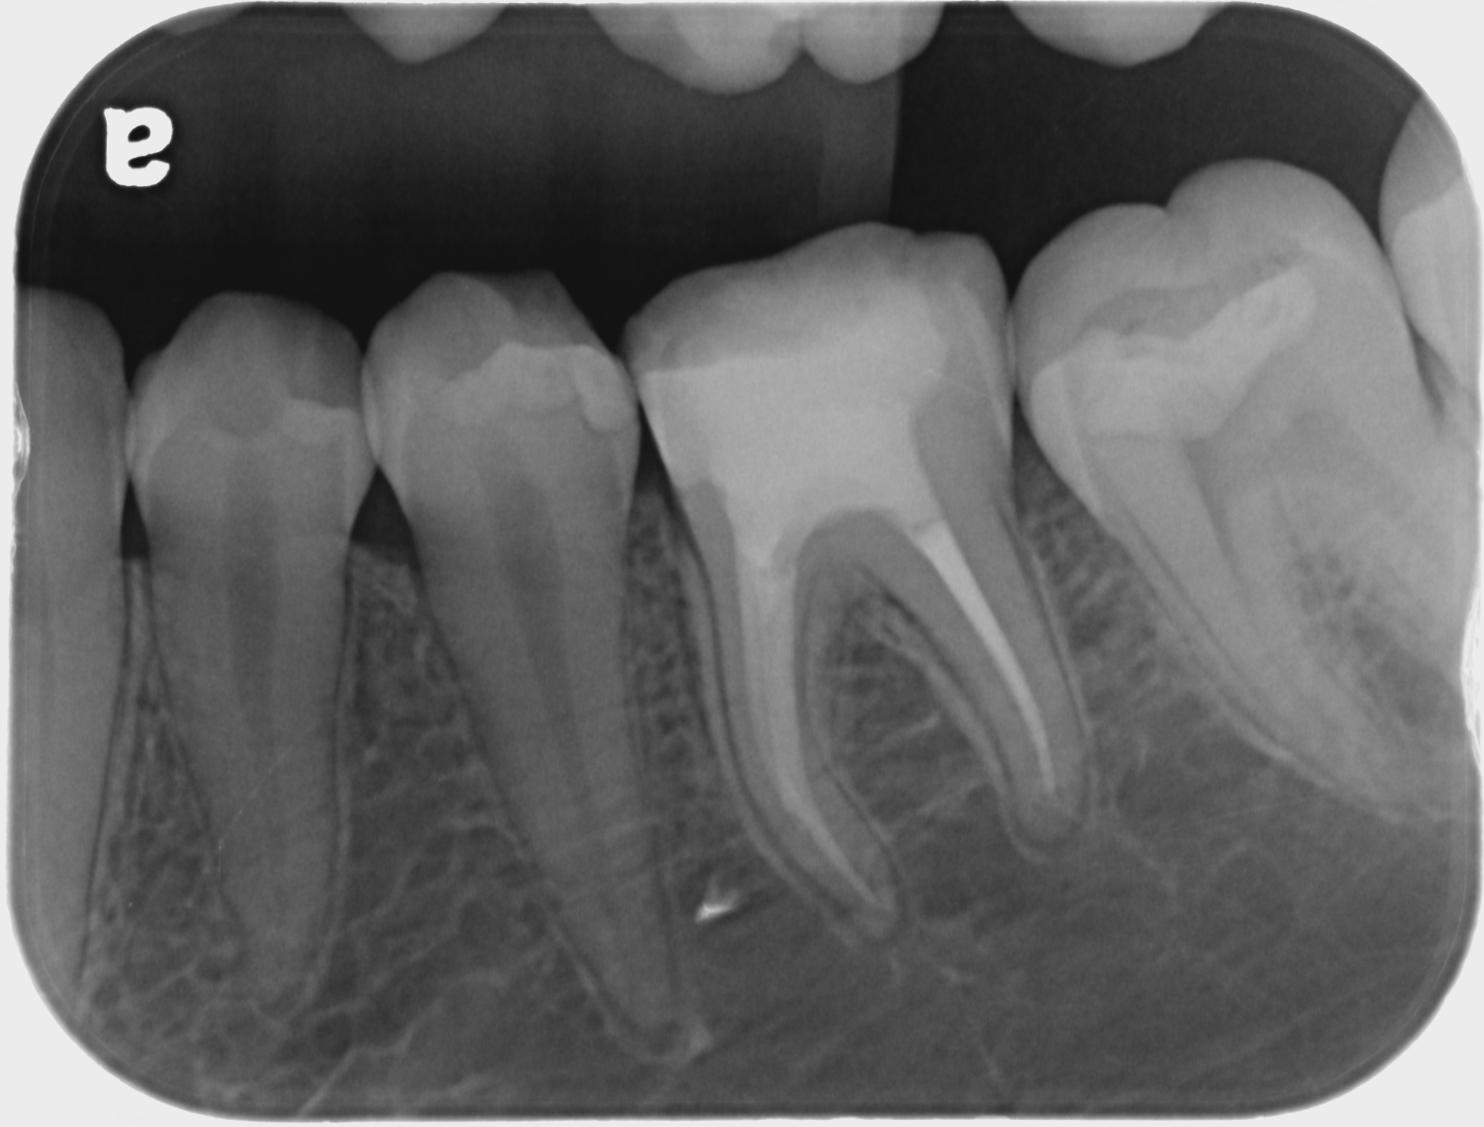

- Endodontic Radiology (Hands On)